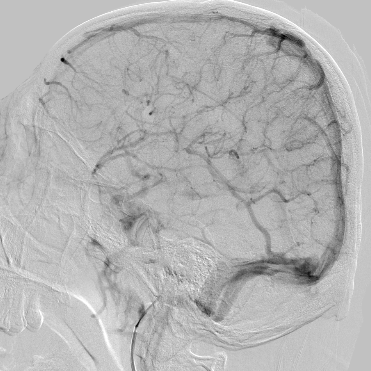

术后即刻

术后症状缓解,左侧肢体肌力基本恢复正常

观察,血管形态还可以,血流顺流

继续观察

术后CT,未见出血